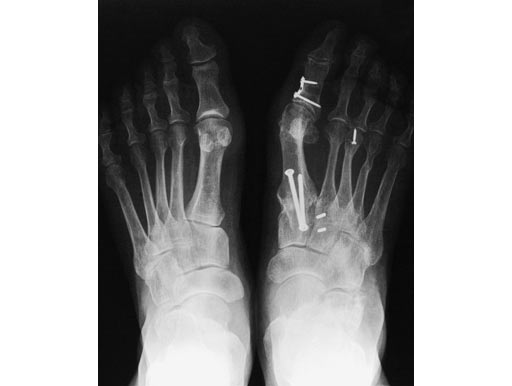

Correction of malunited Akin osteotomy D1 and shortening of the middle phalanx D2 of a flexible hammer toe using a Locking Two-Hole Plate for each correction.